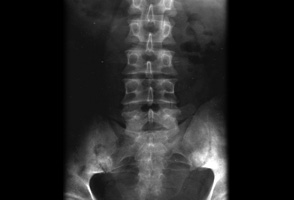

Primeira investigação

- radiografias simples:

radiolucência linear nos pares interarticulares

deformidade em cunha dos corpos vertebrais, tipicamente na parte anterior; deformidade cifótica, apenas a metade anterior do corpo vertebral está envolvida em fraturas por compressão